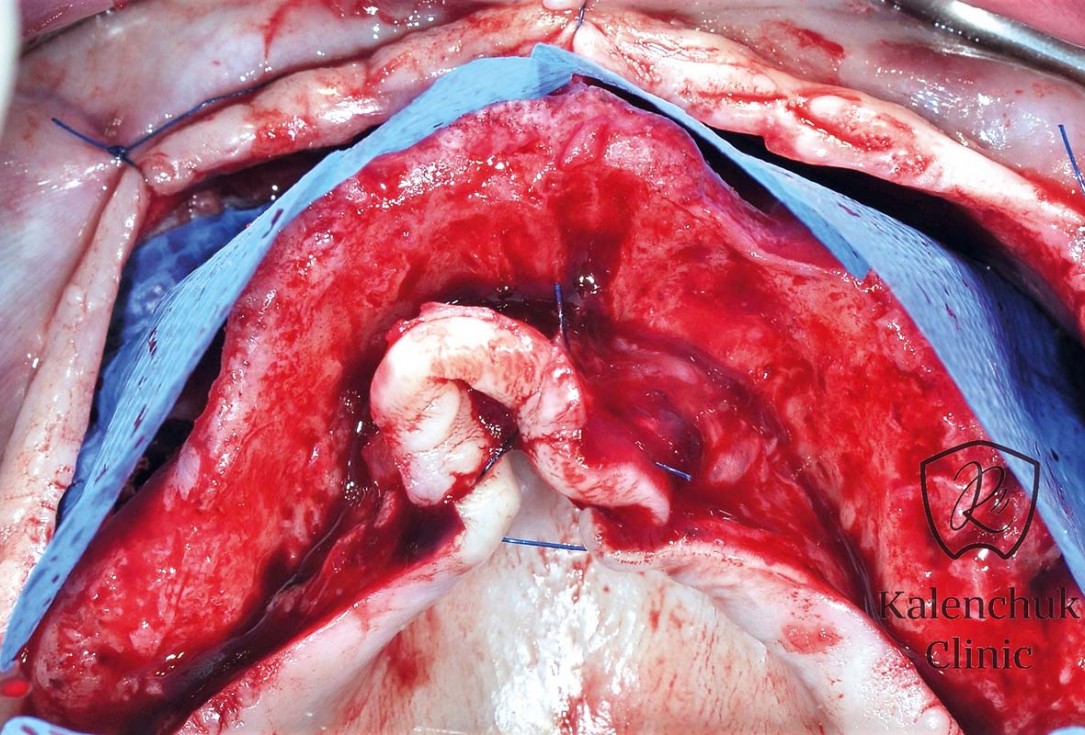

04/23 - Intra-operative view. Alveolar ridge preparation.

GBR of the edentulous maxillary ridge using permamem®, cerabone® and autologous bone chips - Dr. V. Kalenchuk